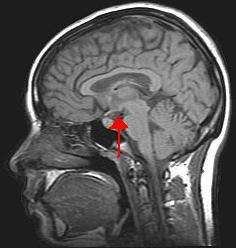

Image of the human head with the brain. The arrow indicates the position of the hypothalamus.

Brain imaging involves analyzing activity within the brain while performing various tasks. This allows us to link behavior and brain function to help understand how information is processed. Different types of imaging techniques vary in their temporal (time-based) and spatial (location-based) resolution. Brain imaging is often used in cognitive neuroscience.